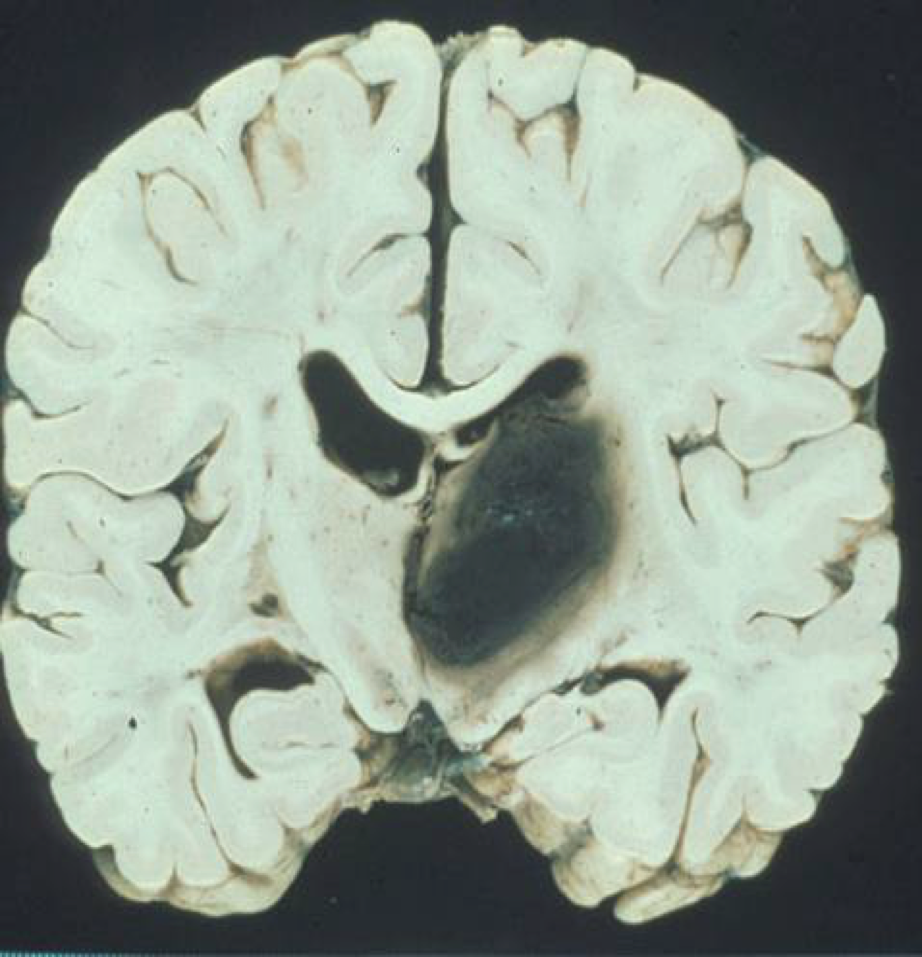

What is this?

intracerebral hemorrhage

What is the leading cause of intracerebral hemorrhage?